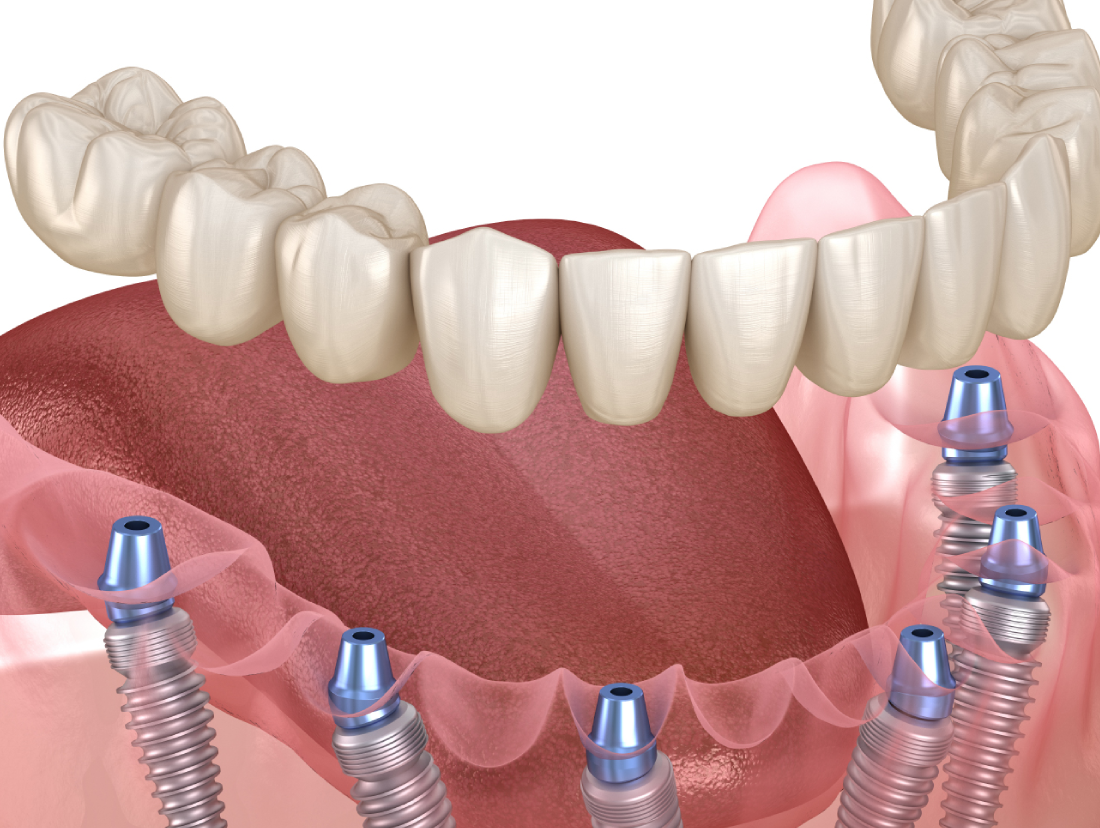

Treatment

Our expert dentists provide world-class care in a state-of-the-art clinical environment.